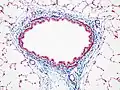

Hematoxilina

La hematoxilina es un colorante nuclear. Hay variedad de ellas siempre usando la base de hematoxilina extraída del árbol palo campeche. Existe la hematoxilina de Mayer, de Harris, y otras. Utilizado con un mordiente, la hematoxilina tiñe los núcleos celulares de color azul violeta a negro. Con gran frecuencia se utiliza en combinación con eosina en la coloración H&E (hematoxilina y eosina), una de las más comunes utilizadas en histología.

Eosina

La eosina se utiliza más frecuentemente como contracoloración de la hematoxilina, impartiendo un color que va del rosado al rojo al material citoplasmático, membrana celular, y algunas estructuras extracelulares. Además imparte un fuerte color rojo a los eritrocitos. La eosina puede ser utilizada también en algunas variantes de la coloración de Gram, y en muchos otros protocolos de tinción. De hecho existen dos compuestos muy estrechamente relacionados (aunque no iguales) conocidos como eosina. El más frecuentemente utilizado es la eosina Y (también conocida como eosina amarillenta) ya que posee una tonalidad amarillenta muy suave. El otro compuesto conocido como eosina es la eosina B, también conocida como eosina azulada o rojo imperial, la cual posee una suave tonalidad azul. Los dos colorantes son intercambiables, y el la utilización de uno u otro es más una cuestión de preferencia y tradición.